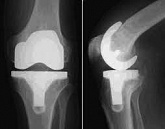

Endoprothetik des Kniegelenks

In den späten Stadien der Arthrose des Knies durch eine ausgeprägte Begrenzung der Bewegung begleitet, konstant starke Schmerzen, körperliche Unversehrtheit Verformung bis zur Genesung der einzige Weg ist der Ersatz des betroffenen Gelenks für eine künstliche - Endoprothetik.

Diese Methode ermöglicht es Ihnen, die richtige Form des Gliedes, eine vollständige Palette von Bewegung im Gelenke, zu entlasten ständige Schmerzen und Knirschen bei Bewegung und als Ergebnis wieder herzustellen, signifikant dem Patienten Lebensqualität zu verbessern.

Im Folgenden sind Röntgenaufnahmen und Fotografien, die die Strecke der Bewegung in der betroffenen Gelenke vor und nach der Operation veranschaulichen.